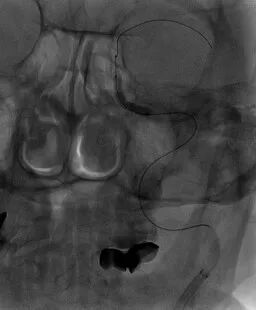

◆ 导引导管置于左侧颈内动脉C1段,微导丝通过狭窄段置于左侧大脑中动脉M2段。

导丝怎么扩重磅!NOVA颅内药物球扩支架湖北首例植入!_https://www.jmylbn.com_新闻资讯_第9张

导引导管到位,导丝通过病变